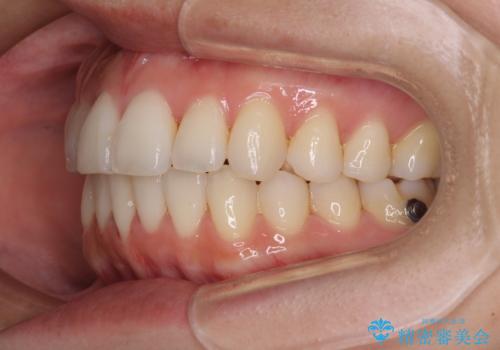

前歯のクロスバイト インビザラインによる矯正治療

- 上下のクロスバイトと前歯のデコボコを気にして来院された患者様です。

インビザラインを用い、IPR(歯と歯の間を削る)と歯列全体を拡大させることで、歯並びを整えていくこととしました。

治療を急いでいらっしゃらなかったため、のんびりと治療を進めていきました。3年以上の期間を要しましたが、きれいな口元に仕上がりました。